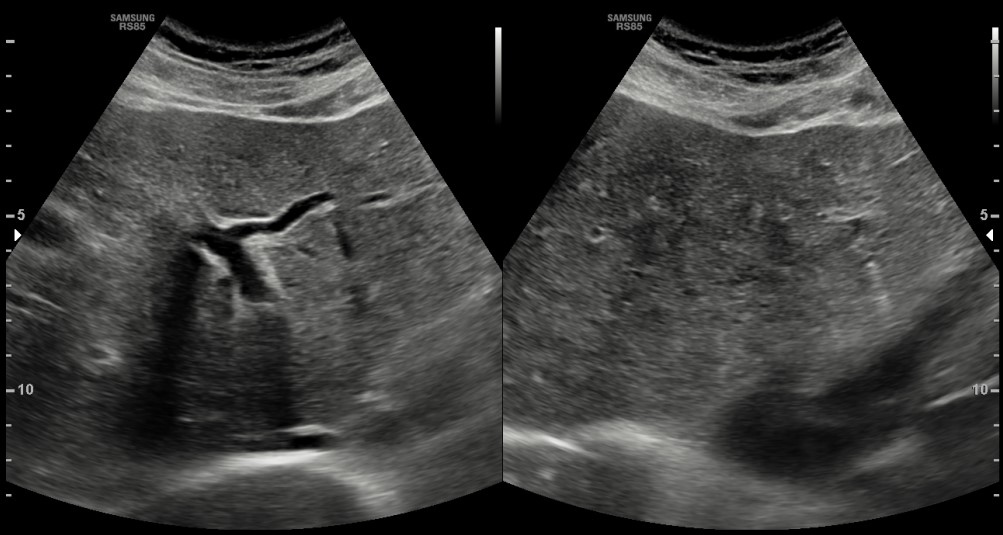

[366,Hepatobiliary [HB]] 62/M,Abnormal finding on upper abdominal ultrasonography during a health check-up

Hepatobiliary [HB]

US,

What is the most likely diagnosis?